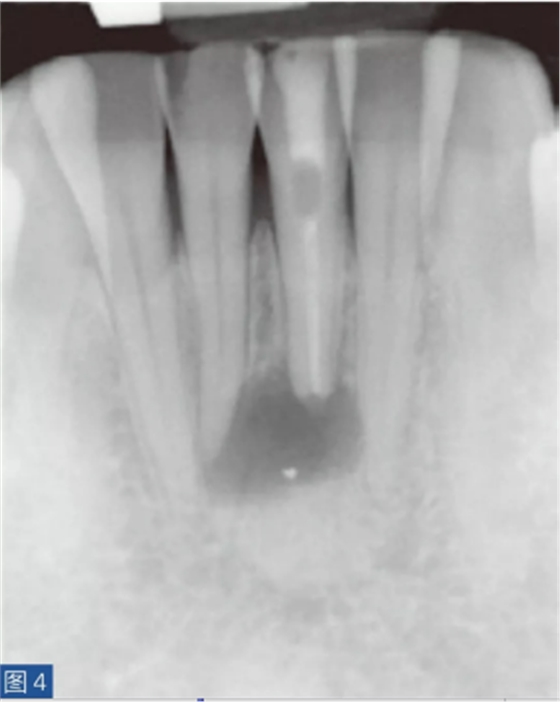

牙齒無癥狀的根尖周炎(圖4 和5)是由牙髓壞死引起的,并且通常是在癥狀性根尖周炎之后發(fā)生。因此,對(duì)冷、熱刺激和牙髓電活力測(cè)試無反應(yīng)。叩診無或者引起輕微的疼痛。如果骨皮質(zhì)已經(jīng)發(fā)生改變并且涉及到口腔軟組織,則觸診可引起輕微不適。放射學(xué)檢查,可能出現(xiàn)硬骨板不連續(xù)(破壞)以及根尖周和牙間組織的廣泛性破壞。

圖4:31 牙齒AAP。術(shù)前X線片?;颊咴V叩診和觸診時(shí)有輕微疼痛。

圖5:31 牙齒AAP。根管再治療12 個(gè)月后。